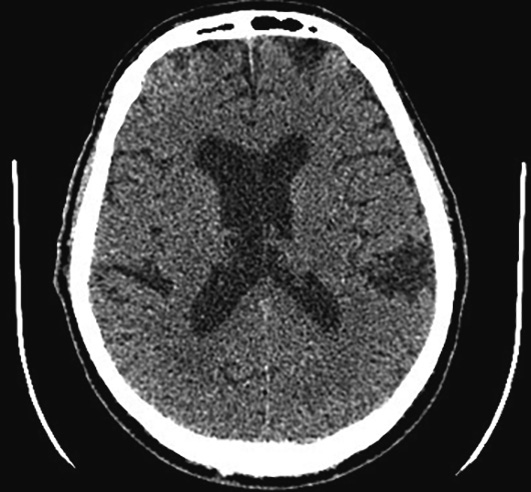

По данным мультиспиральной компьютерной томографии (МСКТ) головного мозга выявлены постишемические кисты теменной доли правой гемисферы (рис. 1). Признаков ОНМК не установлено, шкала ASPECTS (Alberta Stroke Program Early CT Score) — 10 баллов [17].

Рис. 1. Бесконтрастная КТ головного мозга пациента М. при поступлении. ASPECTS 10 баллов. / Fig. 1. Plain brain multislice computed tomography of patient M. on admission. ASPECTS 10.